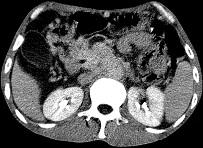

问题 女,50岁,中上腹疼痛,消瘦乏力,影像检查如下图,最佳的诊断是 ( )

选项 A.慢性胰腺炎 B.急性胰腺炎 C.胰腺癌并腹膜后淋巴结转移 D.胰岛素瘤 E.腹膜后淋巴瘤

答案 C